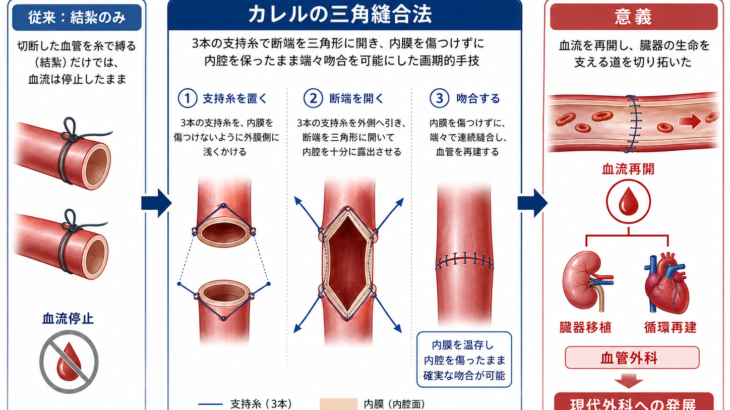

アレクシス・カレル(Alexis Carrel, 1873–1944)は、近代外科、とくに血管外科と臓器移植の成立に大きな影響を与えたフランス出身の外科医・実験医学者です。1873年6月28日にフランスで生まれ、のちに米 続きを読む